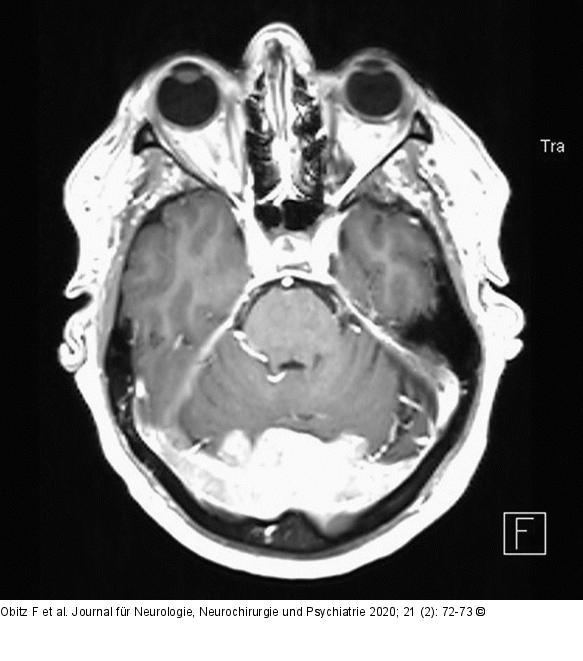

Abbildung 1: Okzipitale Tumormasse

Präoperatives cMRT axial, das okzipitale Tumormasse zeigt. |